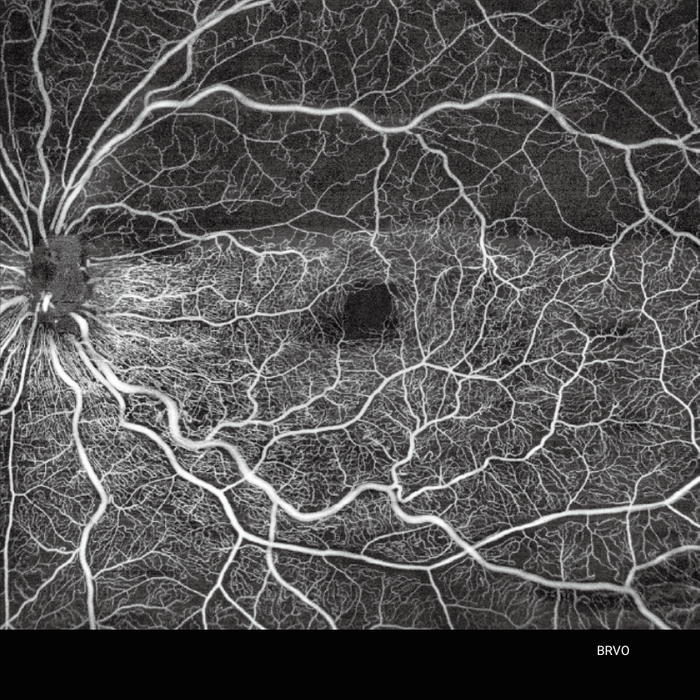

Operating at a 1060 nm wavelength, Yalkaid is especially effective for imaging patients with cataracts or vitreous opacities, with its invisible light minimising fixation distractions. It also features extensive 16 mm line scans and 12 mm 3D/OCTA scans, covering a broader area than traditional SD or SS-OCT systems.

- Scanning depth: Yalkaid's 6 mm depth surpasses the typical 2-3 mm depth of spectral-domain OCT, allowing better imaging of the choroid and sclera.

- Wavelength: the 1060 nm swept-source technology provides better penetration through cataracts and hemorrhages compared to the 840 nm wavelength used in many standard OCT systems.